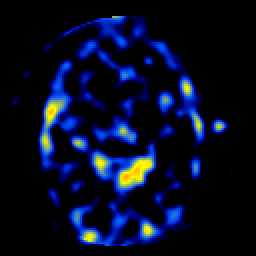

SPECT TL Study #7 -- Slice #28

[Home][Help][Clinical][Tour 1][Tour 2][Tour 3] Slice 28